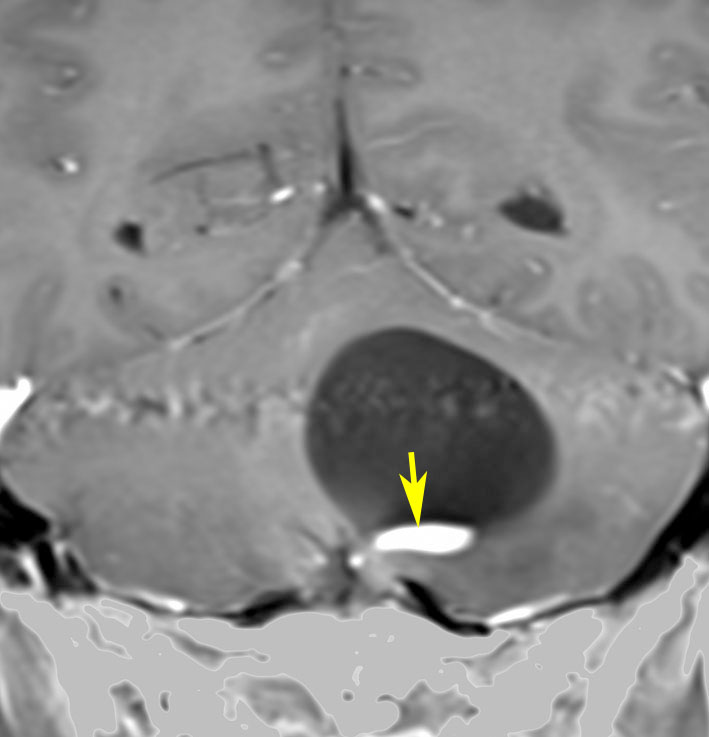

- MRIでは,のう胞(袋に水がたまったようなもの)を高頻度に認めます

- 腫瘍の本体は造影剤で増強効果をうけて白く丸く映ります

- 腫瘍はたいてい丸くてはっきりした形にみえます

左小脳にできた小さな のう胞性血管芽腫です。矢印の先にある小さな塊だけが腫瘍で周囲は腫瘍から染み出した液体が溜まっています(のう胞といいます)。右側は血管撮影とMRIを組み合わせた画像で,腫瘍に動脈が流入しているのが見えます。

簡単な手術となる例

左右の写真は異なった患者さんのものです。両者ともに,大きな嚢胞(水たまり)を伴う小脳内部の小さな血管芽腫です。右の方に小さく白い塊(黄色の矢印)が見えるのですが,それだけが腫瘍で,濃い灰色に見える部分はのう胞といって液体がたまっているだけです。

これはとても(といっては何ですが比較的に)簡単な手術例です。小脳失調によるふらつきや水頭症よる頭痛と嘔吐などを出しますが,手術後に症状は改善します。

一般に小脳半球という場所にできたものは大きくても手術の成功率はとても高いです。小さいものでは場所と症状によってはガンマナイフなどの放射線治療も有効なことがあります。しかし,手術で摘出できるものは摘出した方が確実に治ります。